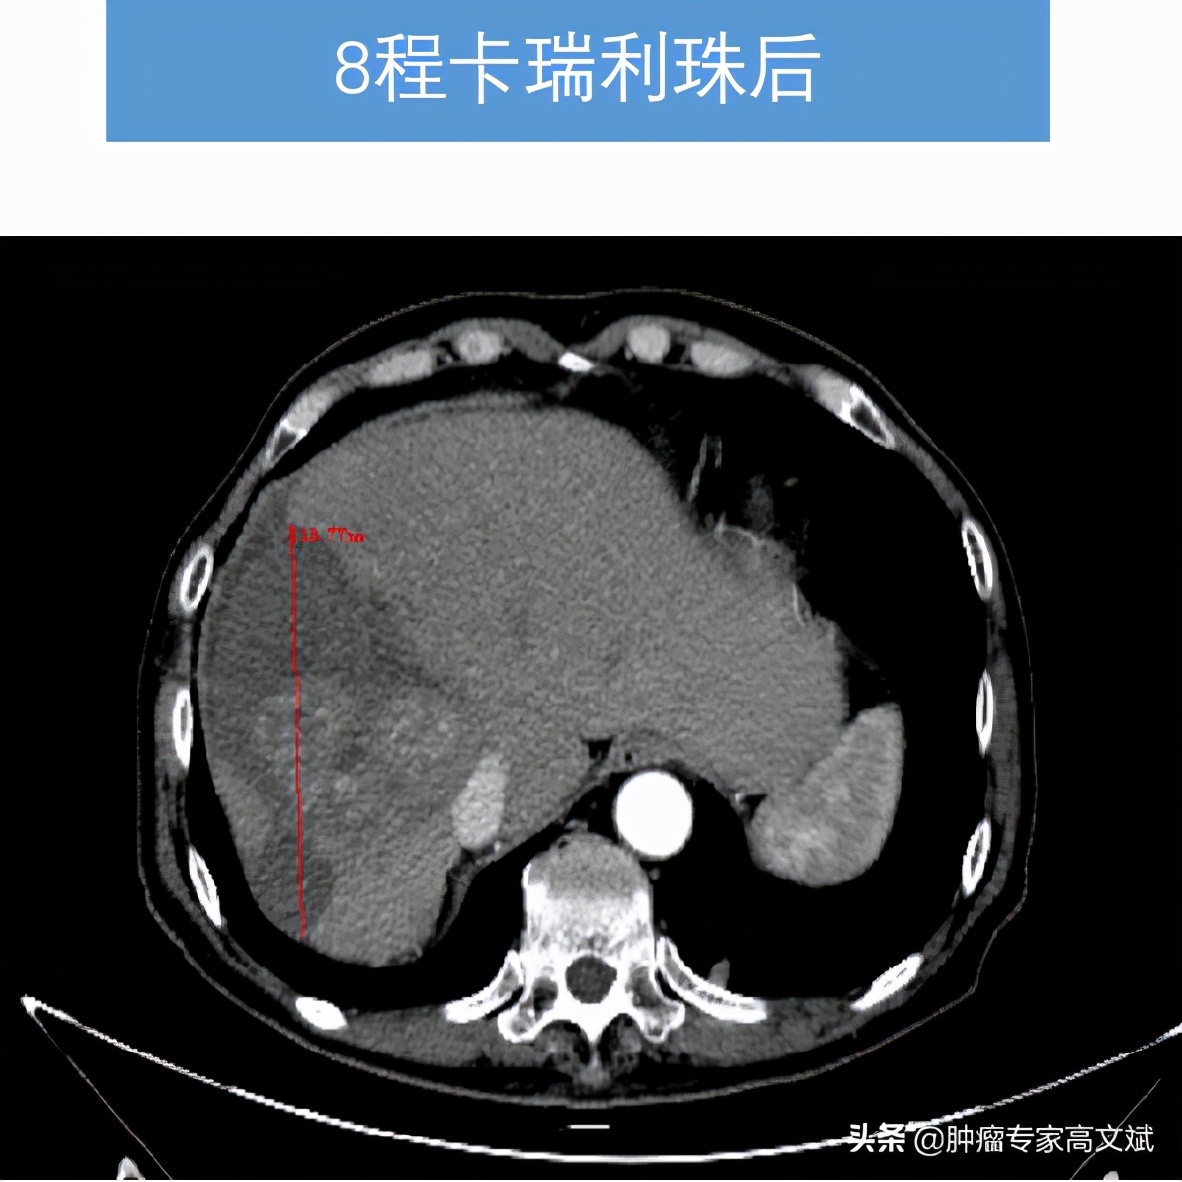

看着患者的一般情况还好,所谓的身体状况不佳主要还是前边治疗的不良反应所导致的。我们还是决定给患者实施一个单药的免疫治疗来控制肿瘤的生长,又不过分增加患者的不良反应。就这样患者也接受了我们的建议,我们为患者实施了国产的免疫制剂卡瑞利珠单抗(艾瑞卡)200mg,每2周一次使用。让我们没有想到的是,患者治疗2个周期以后,肿瘤标志物AFP出现了陡坡样的下降,肝脏疼痛也出现了缓解,每天躺在床上的老陈已经开始下床活动,饮食量等情况也明显的改善,对于治疗患者也有了明显的信心。就这样,治疗了8个周期以后,老陈的肝脏肿瘤明显缩小了,肺内转移灶也有消失,肿瘤标志物则是更早地恢复了正常,止痛药也完全的不再使用了。对于老陈来说,剩下的事情就是每月来罗湖医院肿瘤科输注两次卡瑞利珠单抗(艾瑞卡)就可以了。